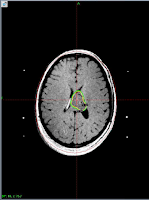

Complete resolution after one year of Gamma knife Treatment.

At GKRS                             After one year                              After Two years